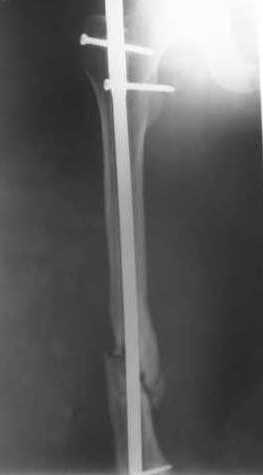

Как обещал, выкладываю рентгенограммы нашего пациента.

Пациенту М., 30-ти лет, 1,5 года назад в одной из московских больниц был выполнен остеосинтез бедренной кости штифтом UFN (диаметр штифта 9 мм).

К нам больной поступил с признаками ложного сустава бедренной кости, перелома

штифта и дистального блокирующего винта (images 1,2,3).

27 марта выполнено удаление блокирующих винтов (сломанный винт пришлось высверливать цапфен-бором), сломанного штифта (дистальный фрагмент удален через канал, образованный разверткой из коленного сустава - image 4),

рассверливание костно-мозгового канала, реостеосинтез штифтом UFN (при проведении штифта в дистальном отломке мы использовали поляризующий винт, диаметр штифта 10 мм). После операции в связи гемартрозом дважды (на 1 и 3 сутки) выполняли пункцию коленного сустава. Сейчас признаков скопления жидкости в полости сустава нет. Послеоперационные рентгенограммы - images 5, 6, 7.